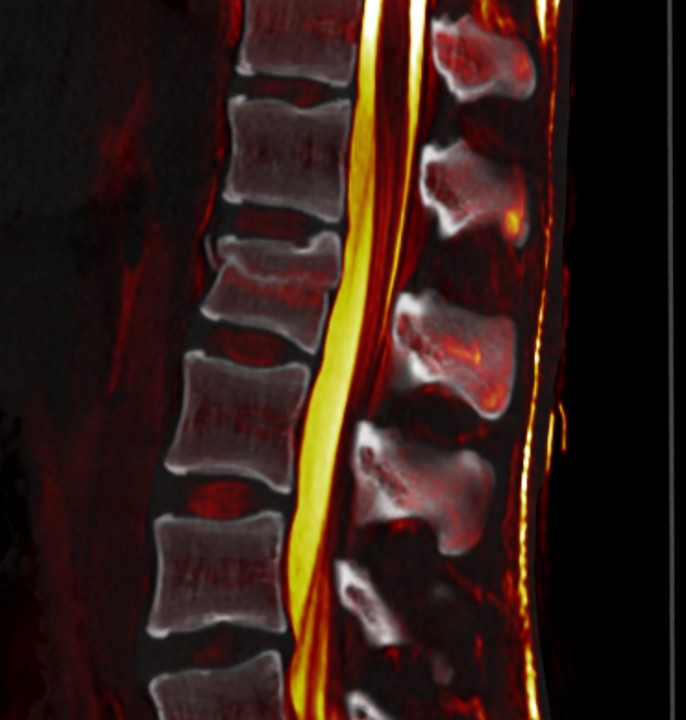

Existen dos vías principales del dolor: la vía rápida y la vía lenta. La vía rápida transmite señales agudas y punzantes, mientras que la vía lenta lleva señales sordas y persistentes. Estas señales viajan desde la médula espinal hasta diferentes áreas cerebrales, incluyendo la corteza somatosensorial, que interpreta la intensidad y la ubicación del dolor, y la amígdala y el hipotálamo, que desempeñan un papel importante en la respuesta emocional al dolor.